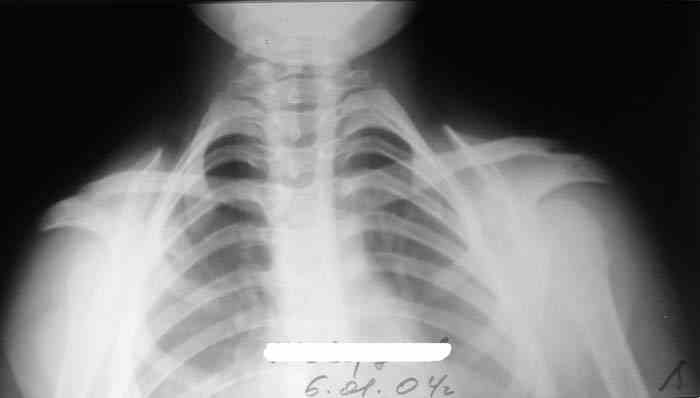

Девочка, 9 лет. Жалобы на деформацию верхнего плечевого пояса.

Объективно: приведение обоих надплечий, объем движений в плечевых суставах в полном объеме, общесоматический статус без патологии, УЗИлопаточных областей - без патологии.

Возможно речь идёт о добавочных шейных рёбрах, для уточнения целесообразно сделать боковую рентгенографию.

Hi! There are some winging of scapulae as at Long thoracic nerve pulcy.May be EMG will be helpfull

Больная на Вашей фотографии довольно похожа на Cleidocranial Disostosis. Пришлите снимки плечевого пояса. Это может быть недоразвитие или отсутствие ключиц.

Наличие ключиц на прямом снимке, снимает диагноз врожденного отсутствия ключиц.

Мне кажется, случай похож на Poland's Syndrom, синдром встречается при врожденной паталогии, когда отсутствует грудные мышцы (pectoralis), в большинстве случаев односторенне, и пластические хирурги рекомендует операцию.

Предлагаю пока рабочим диагнозом считать: "Врожденная аномалия грудной клетки. Добавочные шейные ребра".